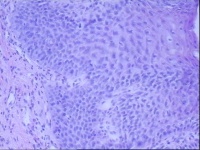

贲门黏膜,请教老师们

性别

男

年龄

59岁

临床诊断

一般病史

胃疼6年

标本名称

贲门黏膜

大体所见

灰白色小组织5块,直径约0.1-0.2CM。

图1